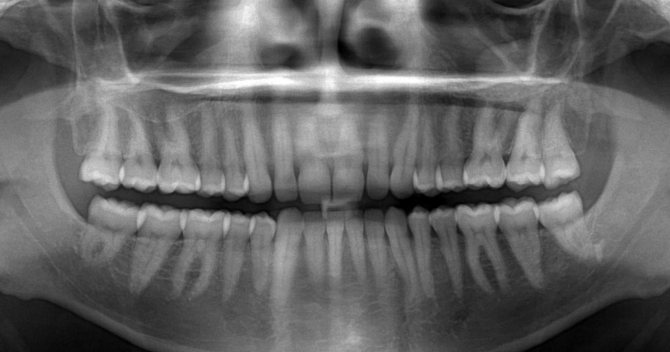

Общепринятым считается наличие 32 зубов у взрослого человека включая «восьмерки». Но сегодня наше питание настолько изменилось, что количество зубов уменьшается. Все это связано с употреблением слишком мягкой переработанной еды.

Вывод: 32 постоянных зуба у человека – это стандартная норма, вместе с «мудрыми» зубами. Но у многих людей вырастает всего 28 постоянных зубов, и это стоматологи также относят к норме, говоря о том, что в ходе эволюции «мудрые» элементы могут и вовсе исчезнуть.

Когда сформирован полный ряд из 14 зубов на верхней челюсти и стольких же на нижней, третьи моляры всё ещё остаются в зачаточном состоянии и только ждут своего времени, когда от их прорезания начнёт ныть десна. Они только готовятся занять своё место. Всё это происходит потому, что вследствие долгих лет эволюции человечество утратило необходимость пережёвывать жёсткую пищу, а значит, отпала потребность в большом количестве зубов, которых у наших предков изначально было аж 44.